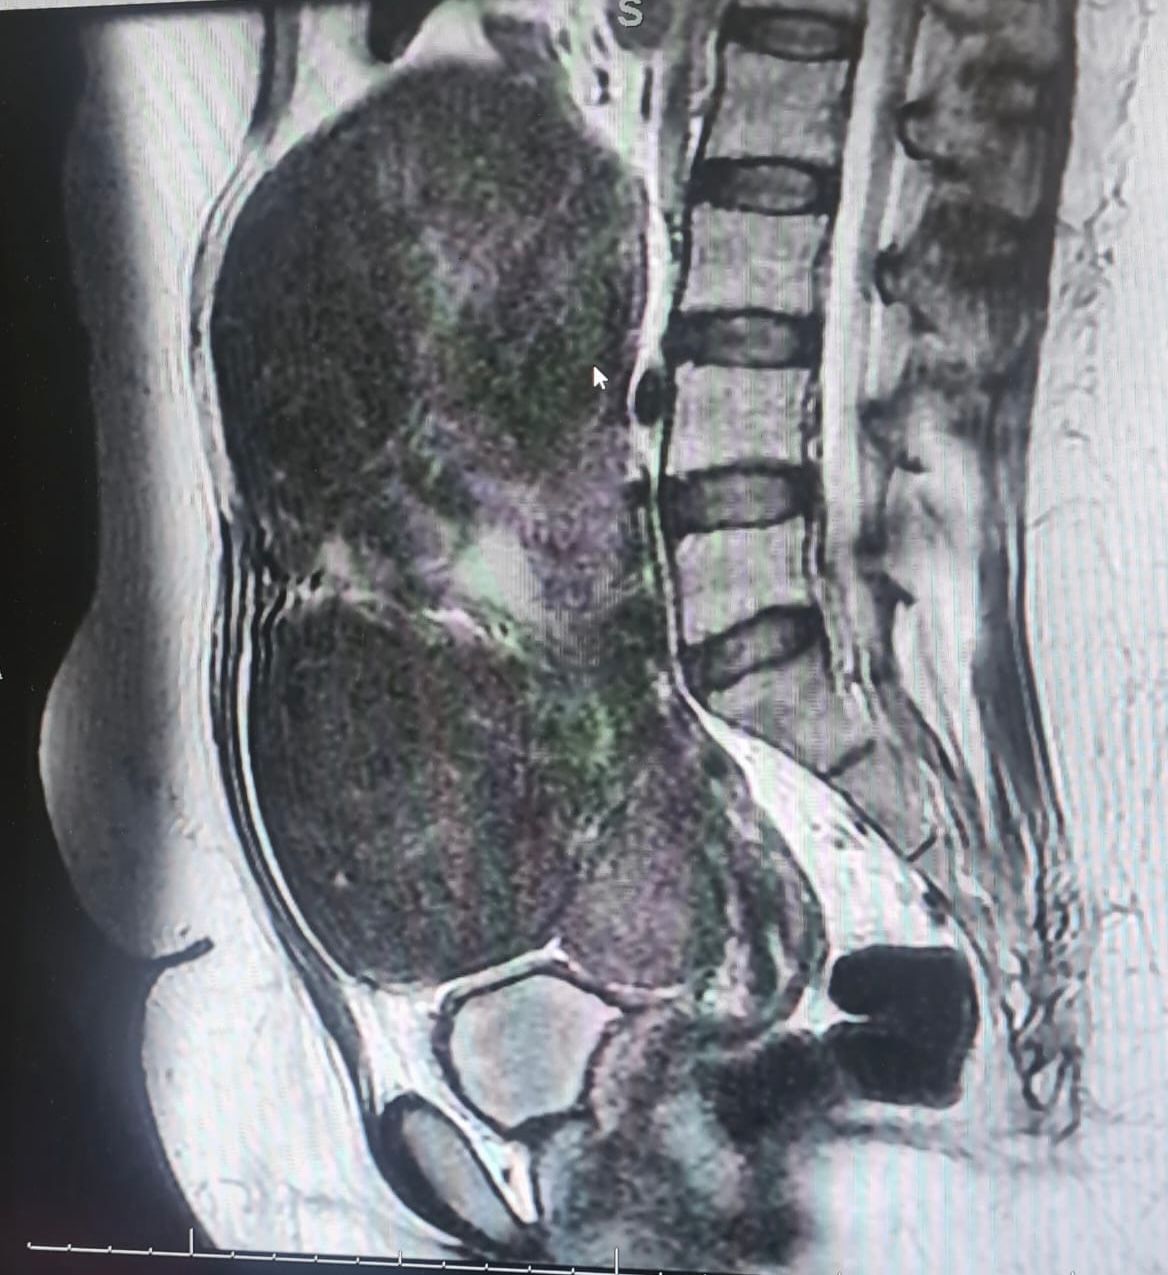

نجح فريق طبي بقسم النساء والولادة بمستشفى القطيف المركزي، في استئصال ٣ أورام عضلية بالرحم من سيدة تبلغ من العمر ٤٨ سنة، بلغ وزن أكبرها ٤ كيلو و١٠٠ جرام.

و بعد عمل الأشعة الصوتية و أشعة الرنين تبين وجود عدة أورام ليفية حميده تملىء تجويف البطن أكبرها بحجم اكثر من ٢٠ سنتيمترًا.

وخضعت المريضة لعملية استغرقت ٣ ساعات تم خلالها استئصال ٣ أورام، بقيادة الاخصائي د. شيماء الجشي، والاخصائي د. إسراء توفيق، والطبيب المقيم فاطمة غواص، وتحت إشراف الاستشارية د. ريم الدوسري رئيس قسم النساء والولادة بالمستشفى.

وتجرى مثل هذه العمليات بشكل مستمر، و لكن حجم ووزن الورم المستئصل يعد كبيرا جدا، و ليس من المعتاد استئصال أورام بهذا الوزن.